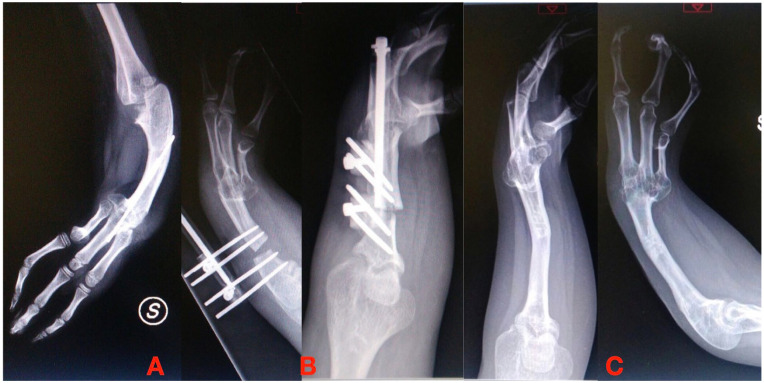

使用外固定架是骨科医生治疗许多临床疾病的文化背景的一部分。多年来,固定架的设计和生物力学知识导致了不同的解决方案和技术,骨延长及其更好的理解与外固定架的发展和牵张成骨生物学原理的应用一起出现。作者对儿童上肢使用外固定架和延长系统进行了文献综述。尽管外固定架在上肢的应用比下肢的应用要有限得多,但有外伤、先天性、肿瘤和感染性病因的迹象。然而,尽管钢板、螺钉和髓内延长钉的新系统得到了广泛应用,但何时使用外固定的问题仍未得到解决。另一个争论点是使用单侧或圆形框架肱骨延长和纠正前臂畸形的多发性遗传性外骨骼疾病(MHE)或桡骨纵向缺陷后遗症。单轴固定架在所有检查区域的骨骼延长中都保持着突出的作用,尽管其作用可能被机动髓内钉所超越,特别是在肱骨延长方面。六足系统可能代表了未来多平面前臂畸形的矫正;然而,为了更好地验证其应用和优势,需要在更大的系列上进行多中心研究。

The use of external fixators is part of the cultural background of orthopedic surgeons in treating numerous clinical conditions. Over the years, fixator design and biomechanical knowledge have led to different solutions and techniques, and bone lengthening and its better understanding come together with the development of external fixators and the application of the biological principle of distraction osteogenesis. The authors conducted a literature review about using external fixators and lengthening systems in pediatric upper limbs. Despite the applications of external fixators in upper limbs remaining much more limited than those of the lower limbs, there are indications of traumatic, congenital, tumor, and infectious etiologies. However, despite the spread of new systems of plate and screws and intramedullary lengthening nails, the problems about when to use external fixation remain unsolved. Another debated point is about using monolateral or circular frames for humeral lengthening and the correction of forearm deformities in multiple hereditary exostoses disease (MHE) or radial longitudinal deficiency sequelae. Monoaxial fixators retain a prominent role for skeletal lengthening in all the districts examined, although their role could be outclassed by the motorized intramedullary nails, especially for humeral lengthening. Hexapod systems are likely to represent the future for the correction of multiplanar forearm deformities; however, multicenter studies on larger series will be necessary to better validate their applications and advantages.